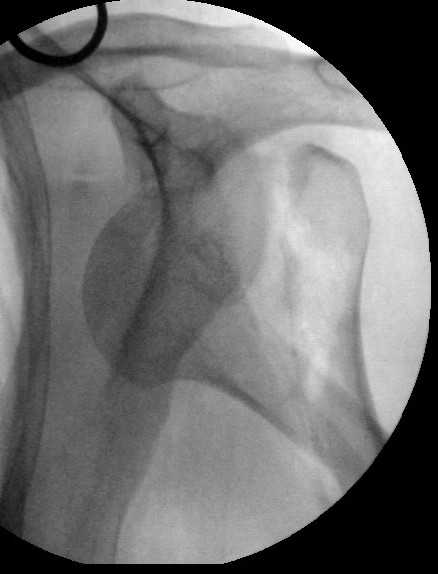

Попытка закрыто изменить положение не удалась. Передним доступом сделали открытую репозицию, гленоид без особенностей. Временно фиксировали спицами и остроконечным костедержателем. Фиксировали гвоздем T2 PHN (Stryker). Для профилактики вывихов после введения проксимальных винтов ротировали дистальный отдел кнаружи на 30

градусов как аналог остеотомии по Weber. Снимки в приложении. Комментарии и критика привествуются.

Attempt of closed reduction failed. Open reduction via anterior approach. The head was temporarily fixed by wires and sharp clamps. Fixation by a nail - T2 PHN (Stryker). The distal fragment has been rotated 30 degrees externally after proximal locking for dislocation prevention as "virtual" Weber osteotomy. Images attached.

Comments/critics are welcome.

I have never used that particular implant.

Is there only a single screw in the head?

What was the status of the cuff?

Did you do any sort of anterior capsular repair?

Interesting idea regarding the Weber rotation.